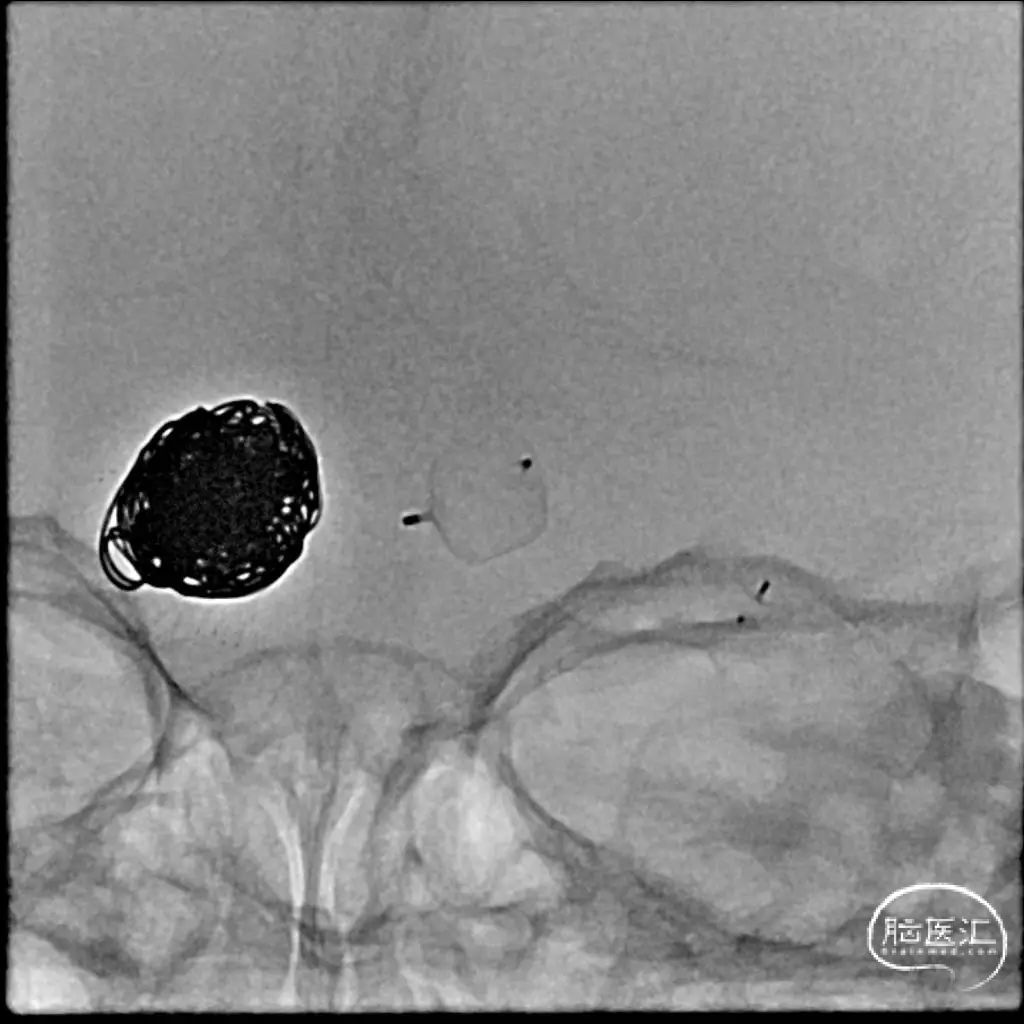

经测量可得动脉瘤宽度平均值为9.1mm,动脉瘤最小高度为8.9mm,最终选择WEB™ SL 11*6。

WEB™经由VIA™微导管缓慢推送至微导管头端。缓慢推出WEB™从种子至萌芽状态,继续向瘤腔内远端缓慢推送WEB™至萌芽至开花间状态;将WEB™送至瘤顶,固定WEB™推送杆回撤VIA™,WEB™完全释放。

经造影可见WEB™尺寸合适,贴合瘤壁。解脱后,再次造影可见动脉瘤瘤腔内有明显造影剂滞留。WEB™对分支血流有影响,使用支架保护分支。

术后6个月随访造影,WEB™充分栓塞,瘤颈残留,WEB™被压缩。